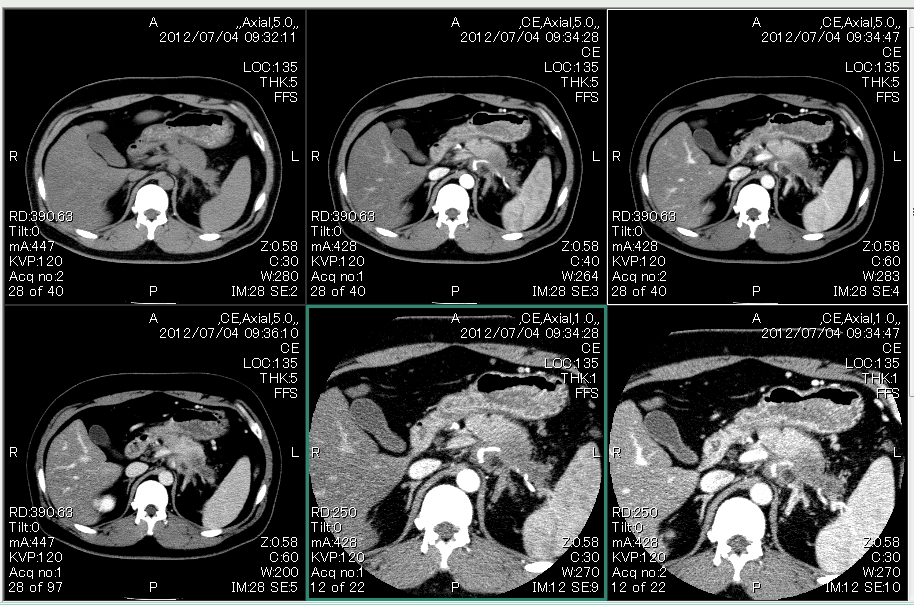

死に至りやすい膵臓がん 超音波内視鏡検査でfive年生存率three倍. 日本の部位別がん死亡数では肺・胃・大腸に次ぐ第4位の「膵臓がん」。年間3万人以上が亡くなっている。 「膵臓がんの患者を診るのは敗戦処理の投手」とある医師は言った。pet(陽電子放射断層撮影装置)検査やct検査に. 胸部・腹部ctでは何が分かりますか? 胸部・腹部ctでは何が分かり. Additionally try. 膵臓癌/問答 kuhp.Kyotou.Ac.Jp. 膵臓癌のステージ別生存率と余命. ④ 画像検査(Ct・mri・ercp・eusなど) 超音波検査や腫瘍マーカーで膵臓癌が疑われる場合には、ctでさらに詳しく調べます。ctとは体にx線を当てて体の断層写真(輪切り状のもの)を撮影するものです。. 膵臓の病気が増加している!知っておくべき3つのポイント. 膵臓癌の臓器別がん死亡率が第4位になったほか、急性膵炎や慢性膵炎などの病気が増加傾向にあります。膵臓は私たちの体の中で重要な働きをしている臓器ですので、その働きや病気について知っておきま. 【膵臓癌の検査】エコー・腫瘍マーカーから最新の検査方法(ct・mri・. 膵臓がんの検査:Ct検査、腫瘍マーカーなどの解説 膵臓がんの検査は血液検査、画像検査、 内視鏡 検査、病理検査など多岐に渡ります。 膵臓がんは 悪性度 が高く、進行も比較的早いと考えられます。. 膵臓がんの症状と治療法 tumormarker. 膵臓がん早期発見・早期治療が難しいがん. 膵臓を大きく分けてthreeつに分けると、十二指腸に近い部分の膵頭部、中央の膵体部、脾臓に近い膵尾部となります。. 肝臓・胆道・膵臓 日本小児外科学会. 膵臓は胃の背中側にある臓器で,消化酵素を分泌する外分泌機能とインスリンやグルカゴンなどのホルモンを分泌する内分泌機能を持っています.膵炎には急性膵炎と慢性膵炎があります.. 【ct画像あり】膵臓の場所を図で解説!痛みが出るのはココ! 人間ド. 膵臓がんの診断には、造影剤を用いたマルチスライスCt(mdct)検査が推奨されています。 mdctは、1回のスキャンで多方向からの観察が可能です。 また、造影剤を用いることで、血流や病変を詳しくみることができます。.

膵がん:膵臓の病気と治療 東京医科歯科大学肝胆膵外科. Ct で膵臓のなかに 1.5cm ほどの影があるといわれています.半年後に再検査をすることになっていますが,膵臓癌ではないかと心配です.このまま放置しておいていいのでしょうか?. 膵臓がん 治療:[国立がん研究センター がん情報サービス 一般の. 膵臓がんの治療では、手術でがんを切除できると考えられる場合、手術の実施が推奨されています。 手術ができるかは、Ct検査などの所見を総合し、「切除可能性分類」に従って、肝臓や肺などへの転移がないか、大きな血管にがんが広がっていないか、などの点から、以下の3つに分類されます。. 膵臓がん 検査:[国立がん研究センター がん情報サービス 一般の. 膵臓がんが疑われる場合、腹部超音波(エコー)検査、Ct検査、mri検査が行われます。 これらの検査から診断に至らない場合には、病状に合わせて、超音波内視鏡検査(eus)、mr胆管膵管撮影(mrcp)、内視鏡的逆行性胆管膵管造影(ercp)、pet検査などを行い、総合的な判断を行います。. すい臓がんになりました odn:各種サービス. 上腹部Ctの横断像の正常解剖を快適にご覧いただけます。肝臓、胆嚢、膵臓、脾臓、副腎、腎臓といった腹部の実質臓器に加えて、食道、胃、十二指腸、小腸、結腸といった消化管にも対応しています。. 膵臓がん|一般社団法人 日本肝胆膵外科学会. 膵臓がんとは 膵臓がんの概要 膵臓がんは、膵臓の中の膵管上皮細胞から発生したがんです。診断と治療の非常に難しいがんで、診断がついた段階で手術できる患者さんはわずかに約20%に過ぎません。. 【ct、mri画像あり】膵嚢胞とは?鑑別・症状・検査・治療まとめ!. 通常のCtの目的は膵臓癌だの腎細胞癌などのスクリーニング目的であり、大腸の評価目的ではありません。 ただし、最近のctだと仮想内視鏡モードがあるので、あたかも大腸内視鏡検査をしているかのような画像を得ることができます。. 膵がん:膵臓の病気と治療 東京医科歯科大学肝胆膵外科. Mri. 核磁気共鳴検査。磁石の力で体の中を検査します。Ct画像と同じような画像が得られますが、mrcpという特殊な条件での撮影では胆管や膵管の描出に優れており、膵がんによる胆管や膵管の圧迫の有無がわかります。. 膵がん|慶應義塾大学病院 kompas. 概要. 膵がんの罹患率は加齢とともに上昇し、forty歳を過ぎたころより急増しています。日本の膵がん罹患率は世界的にみると高く、悪性腫瘍による死因では男性の第five位、女性の第4位を占めています。.

すい臓の検査で腹部ctは有効ではないのですか?造影ctでないと意味が.. 前回の検査結果を聞くと、Ctの検査ですい臓が少しはれている。 い管を挿入して、造影剤という薬を注入して膵臓の血管. 膵臓(すいぞう)がんの検査と診断. 造影Ctにおいて、膵臓周囲の左右に広範な液貯留を認めている様子がわかります。 後腹膜に沿って炎症が広がっていることで、 後腹膜の構造がわかりやすく なっています。. 膵臓(すいぞう)がんについて知っておいてほしいこと 同友会. 膵臓は食事を消化したり血糖をコントロールするなど重要な役割を担う臓器の一つですが、その一方でがんがあっても進行するまで症状に出ない、画像によく映らない、病気の進行が速いといった悪条件が重なっているため、「暗黒の臓器」と呼ばれています。. トリプシン【すい臓(膵臓)関連用語】. トリプシンはすい臓(膵臓)から分泌され、蛋白質の消化酵素の役割を果たします。 タンパク分解酵素であるトリプシンは、食物中のタンパク質を消化するために十二指腸で活性化され、その役割を果たし. 膵臓病q&a myclinic.Ne.Jp. 膵臓の働きや病気についてQ&a形式でまとめてみました。 q膵臓(すいぞう)とは a膵臓は腰椎の1~2番目くらいの高さで、胃の裏側に位置し、十二指腸から脾臓にかけて横に長く伸びている臓器です。. これまでの事⑧~緊急入院と膵臓の腫瘍 あれま膵癌ですかは. あれま膵癌ですかはてさてどうしたものか。 閉塞性黄疸→膵頭癌診断→手術不可でとりあえずの抗がん剤 fifty one才おやじ、2018年7月27日緊急入院からの日々の日記です。 筆不精で不定期となりますが自分の足跡を残すために、つらつらと書いていきます。. 渋谷ヒラハタクリニック|内科・健診・人間ドック・胃カメラ・. 当院では、一般内科、消化器内科の他、慢性膵炎、膵臓が弱い方(膵臓の未病)の診療にも力を入れております。. 膵臓がん 検査:[国立がん研究センター がん情報サービス 一般の方へ]. 肝臓や胆嚢、膵臓など内視鏡で観察できない腹部臓器の病変を診断する際に有効です。 検査方法には、造影剤を使わない単純Ct撮影と造影剤を使う造影ct撮影があり、後者ではより明らかに判定できます。.

【ct画像あり】膵臓の場所を図で解説!痛みが出るのはココ! 人間ド. 膵臓がんの診断には、造影剤を用いたマルチスライスCt(mdct)検査が推奨されています。 mdctは、1回のスキャンで多方向からの観察が可能です。 また、造影剤を用いることで、血流や病変を詳しくみることができます。.

膵臓がんの精密検査(ctやmriなどを使った画像検査など). 膵臓がん(膵がん)の検査方法(生化学的検査、Ct検査、pet検査、腹部超音波検査、超音波内視鏡検査、内視鏡検査、mri検査、mr胆膵管撮影、腹部血管造影検査)について、詳しくわかる解説ページです。. 家にもある!膵臓がん発見の新兵器はあの「飲み物」 〈aera. 難治がんの典型といわれる膵臓(すいぞう)がん。年間の死亡者数は罹患者数にほぼ匹敵し、患者の生存率は極めて低い。早期発見が重要になる. 膵のう胞性腫瘍 国立がん研究センター 東病院. 膵がんが疑われた場合には、膵臓は体の表面からはみえませんので、まず、超音波検査やCt検査を行い、膵臓に腫瘤があるかないかを調べます。また、ct検査では肺や肝臓などのほかの臓器に膵がんが転移していないか調べることができます。. 膵臓がん(膵がん)の検査|オリンパス おなかの健康ドットコム. さらに炎症が強い場合は、膵臓自体に虚血や壊死が生じることがあります。 関連記事)2015年急性膵炎診療ガイドラインに基づくct画像診断のポイント! 急性膵炎のct grade(ctグレード)でチェックすべき点は?.

急性膵炎のctグレードの評価をイラストと画像でわかりやすく解説!. Ct で膵臓のなかに 1.5cm ほどの影があるといわれています.半年後に再検査をすることになっていますが,膵臓癌ではないかと心配です.このまま放置しておいていいのでしょうか?. 上腹部ctの正常解剖 画像診断cafe. 膵臓がんの精密検査(Ctやmriなどを使った画像検査など) 更新日: 2018年10月8日 血液検査など最初の検査で膵臓がんが疑われた場合は、精密検査をして本当に膵臓がんなのか、他の病気なのかを調べることになります。. 膵臓癌/問答 kuhp.Kyotou.Ac.Jp. 急性膵炎のCt画像所見です。 少し時間が経過した、右側の画像では、膵臓の腹側に巨大な液貯留を認めています。 急性膵炎後の仮性嚢胞と診断され、ドレナージ術が施行されました。 症例 70歳代男性 膵腫瘍にて膵体尾部切除後. 腹部造影Ctの横断像です。. 膵臓・胆道の外科 kuhp.Kyotou.Ac.Jp. 消化器病学 S525 講義内容 膵疾患の外科治療. 日時 2007 年 eleven 月 02 日. 奇形 外傷 炎症 腫瘍. 膵臓の解剖. 十二指腸乳頭部癌. 腹部ct検査:肝臓、胆嚢、膵臓の病変を診断します. 目次1 膵臓のct、mri画像診断1.1 膵臓総論1.2 所見からせまる1.Three 膵癌1.Four その他の膵腫瘍2 膵嚢胞性疾患3 血管性病変 膵臓のct. 膵炎/すい臓の炎症/膵臓は日本で作られた文字. 腹膜後器官 腹膜によって腹壁に固定されているものを腹膜後器官という。 腹膜後器官には十二指腸、上行結腸、下行結腸、膵臓、腎臓、副腎、尿管などがある。.